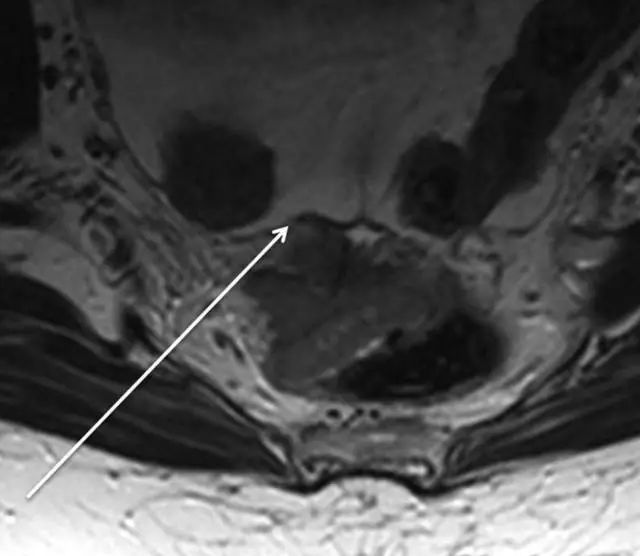

62 岁直肠癌妇女,薄层 T2 加权轴位 MR 图像显示直肠癌,在 9 点钟位置。

箭头显示直肠系膜筋膜。